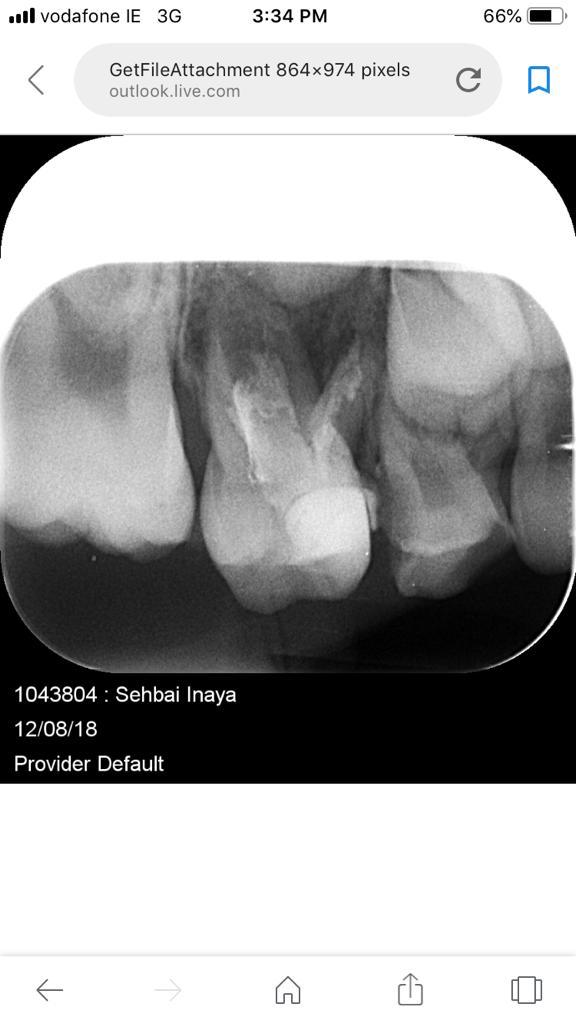

My daughter is 7 and hav deep cavity I took her to dentist one said she need 1 extraction and when I went to pediatric dentist she said she needs 4 extractions which she is going to do altogether same day I am attaching her xrays can any dentist plz advise after looking at the xrays thanks

Her both upper D are definitely for extraction and for her E need to evaluate clinically as well there might get b some Endodontic treatment and space maintainers afterwards

After extraction she will need space maintainer to keep first molar in its place so better to go for RCT to keep this tooth till age 12